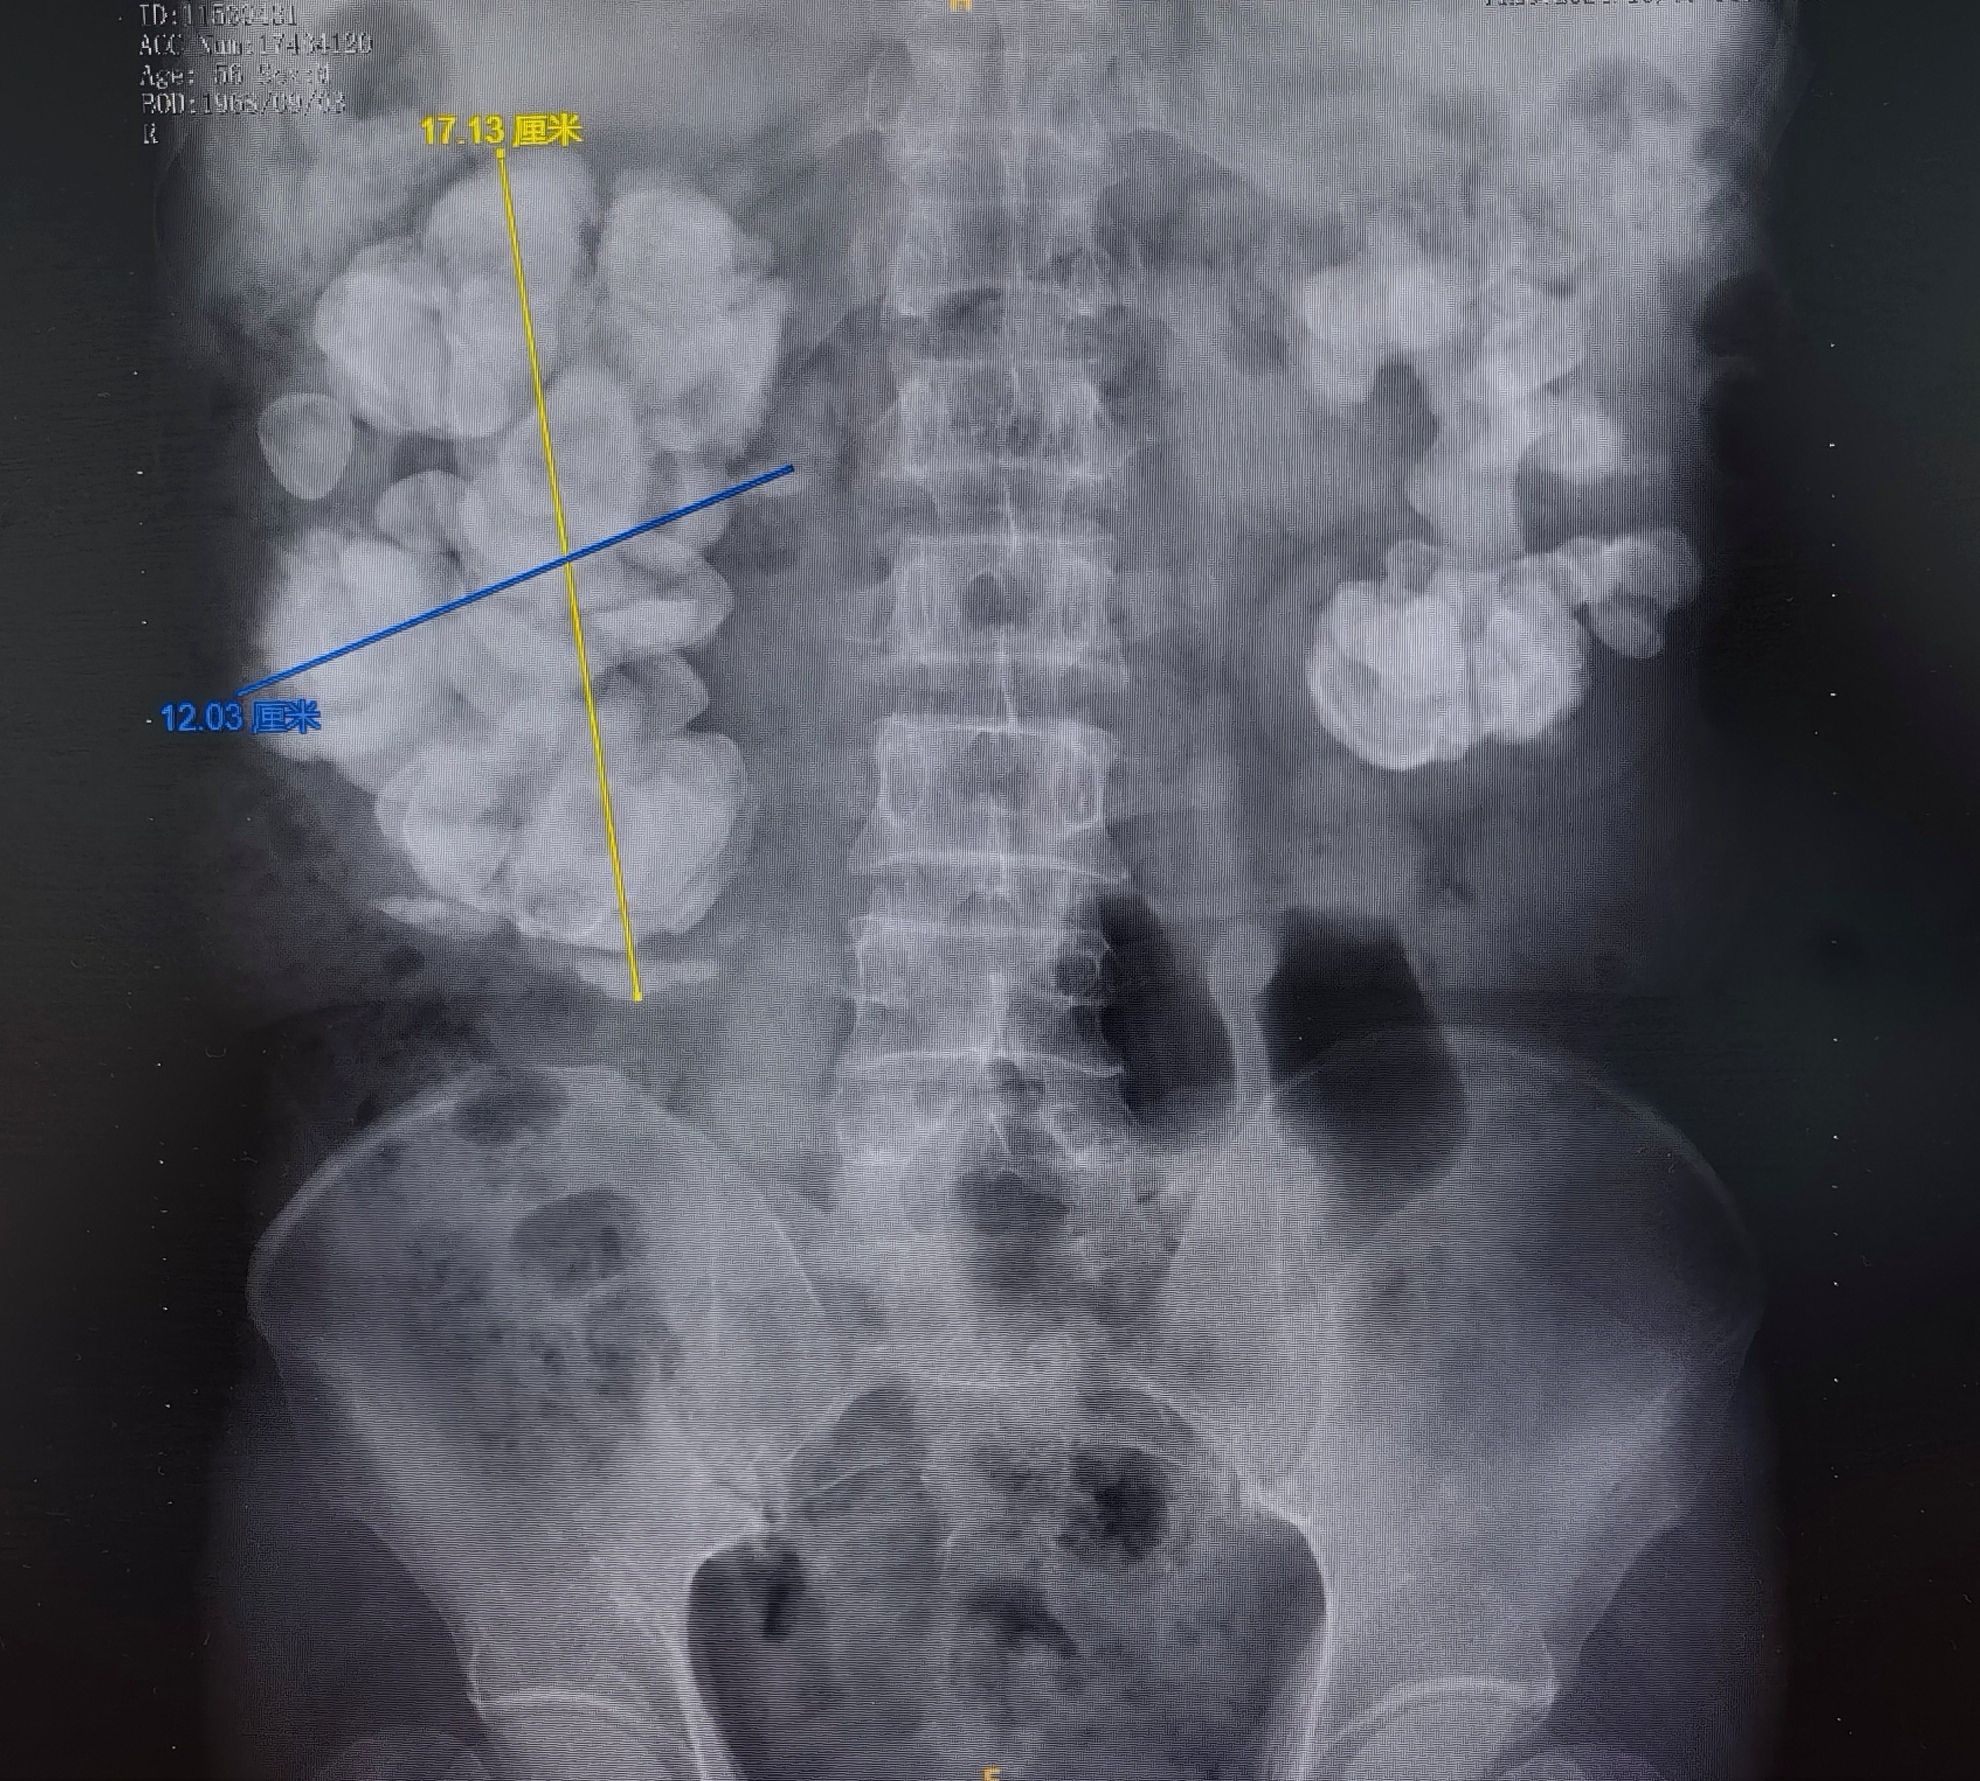

北京清华长庚医院6月11日电(供稿 泌尿外科)影像片子上,患者的双侧肾脏尤其是右肾里赫然矗立着一座"巨石阵",鹿角形肾结石不仅霸占了整个肾脏空间,还嚣张地蔓延生长成了17cm×12cm"大个"。患者辗转多家医院,因取石保肾治疗难度极大,都建议他直接切除右侧肾脏,直到来到了北京清华长庚医院泌尿外科,患者及家人终于等到了他们想要的方案。当所有的右肾结石经历多次手术被清除出来后,竟重达1.7斤。

泌尿外科主诊医师刘宇保接诊后查看患者影像资料,CT示双侧肾脏复杂性巨大肾结石,右肾尤为严重,平均最高CT值达1100-1300HU(代表结石硬度,相当于各种不同结石成分中最坚硬的一类),血肌酐在240μmol/L左右(正常值为<82~95μmol/L),处于肾功能不全代偿期。种种因素导致微创手术治疗难度极大,但患者右侧肾脏功能仍有30%-40%。患者刚50出头,是全家收入来源的主要劳动力,保肾的意愿尤其强烈。切除一侧肾脏,会影响患者另一侧肾脏的代偿能力,若左侧肾脏在手术以后出现结石复发、严重感染等问题,将严重影响到其生活质量。在科室主任李建兴的带领下,以微创取石作为最后的选择,刘宇保和患者一起先行尝试"保肾大作战"方案。